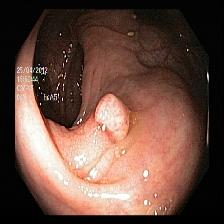

Figure 5 showcases paired examples of raw and LIME-explained images across various classes, providing direct comparisons and highlighting the influence of visual enhancements on the interpretability of the model.

![]() |

| (a) | (b) | (c) | (d) |